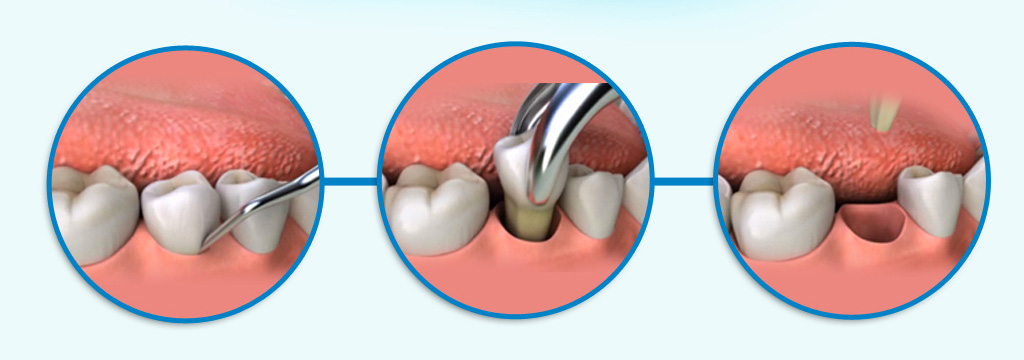

Χειρουργική Στόματος - Στάδια

Η Χειρουργική του Στόματος ασχολείται με στοματικά προβλήματα για των οποίον την αντιμετώπιση είναι απαιτητή η χειρουργική επέμβαση. Παραδοσιακά η χειρουργική του στόματος ανήκει στο ευρύτερο γνωστικό αντικείμενο της Οδοντιατρικής επιστήμης.

Εξαγωγές δοντιών και υπολειμματικών ριζών

Αντιμετώπιση των έγκλειστων δοντιών καθώς και των επιπλοκών που μπορεί να δημιουργηθούν (φρονιμίτης)

Περιακρορριζική χειρουργική (ακρορριζεκτομή)